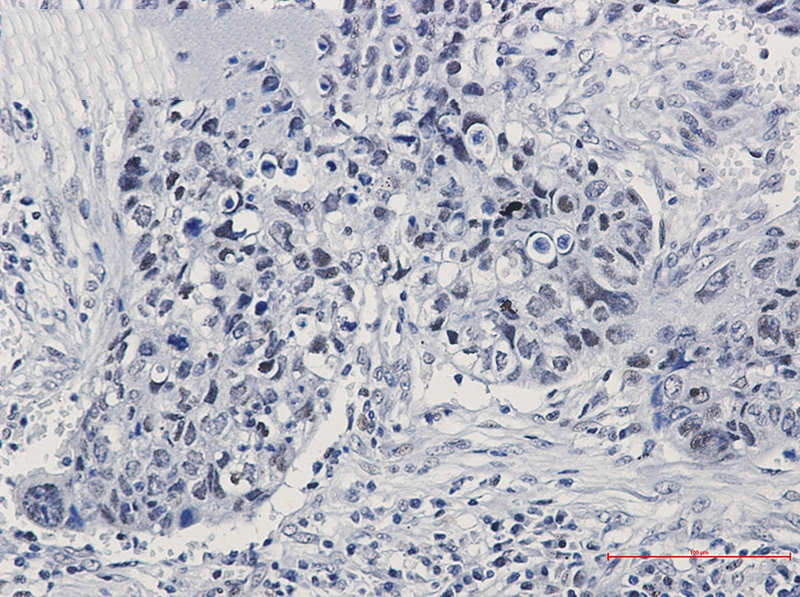

![hnRNP K Rabbit mAb[52342]](https://img1.dxycdn.com/p/s14/2025/0922/633/0084068538848399691.jpg)

Immunohistochemistry of hnRNP K in paraffin-embedded Human lung cancer tissue using hnRNP K Rabbit mAb at dilution 1/50